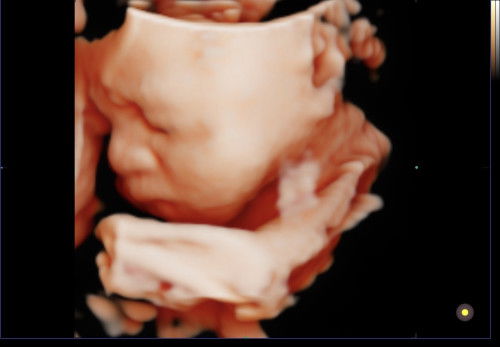

ทีมกรกฎาคม ค่ะ หมอนัด 9 ก.ค. แต่น้องกลับหัวไปรอบแล้วแต่เชิงกรานแม่ไม่ขยาย บวกกับน้องน่าจะตัวใหญ่ เพราะตอนไปซาวน์ 35w น้องหนัก 2638g. น้องเลยกลับมานอนขวางเลย คลอดธรรมชาติไม่ได้แน่ๆ หมอให้เลือกวันคลอดเองเลย เราเลือก 3 ก.ค. ตอนนี้ 37w +3 อยากรู้อาการเจ็บท้องก่อนคลอดอ่ะคะ ว่าอาการเป็นอย่างไร กลัวจะปวดท้องคลอดก่อนถึงวันที่เราเลือก ใครพอทราบอาการช่วยบอกหน่อยนะคะ ยิ่งเห็นรูปที่ซาวน์ ยิ่งอยากเห็นหน้าลูกแล้ว แต่ก็อยากรอให้ถึงวันที่เราเลือกไว้

ทีมกรกฎา ตอนนี้ 26w แล้ว เริ่มเห็นหน้าน้องชัดแล้ว ตอนซาวน์น้องยิ้มให้ 1 ที คุณแม่ๆเริ่มเตรียมของกันยังคะ พอดีท้องแรกยังไม่รู้ว่าจะต้องเตรียมอะไรบ้าง ช่วยแนะนำหน่อยนะคะ #ขอบคุณสำหรับคำตอบค่ะ

ใครคลอดเดือนกรกฎาคมบ้างคะ อยากสอบถามว่าเลือกคลอดเอง หรือผ่าคลอดกันค่ะ ทางนี้ยังตัดสินใจไม่ได้เลย เพิ่งไปซาวน์มาล่าสุด เริ่มได้เห็นเบบี๋ตัวน้อยชัดขึ้นมาหน่อย แต่คิดหนักว่าควรคลอดแบบไหนดี #ท้องแรกคะ #คุณแม่ๆช่วยแนะนำหน่อยค่ะ